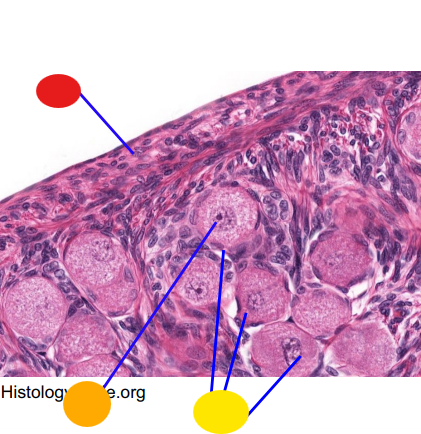

red

primary oocyte

orange

zona pellucida

yellow

granulosa cells

light green

developing thecal cells

What is this

secondary follicle

red

granulosa cells

orange

primary oocyte

what is this

primary follicle

red

granulosa cells

orange

thecal cells

yellow

zona pellucida

What is this

secondary follicle